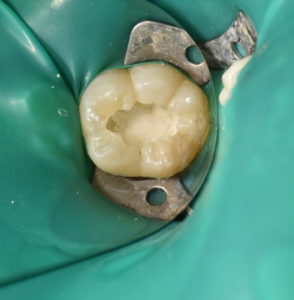

感染防止のためラバーダムを装着し、う蝕を除去していくと大きく2箇所露髄した。周囲にう蝕は存在するものの歯髄自体に変性はなく保存可能と判断した。

一部貧血帯もあったため冠部歯髄を除去し、MTAセメントにて歯髄を保護をした後、仮封を行い1回目の処置は終了した。